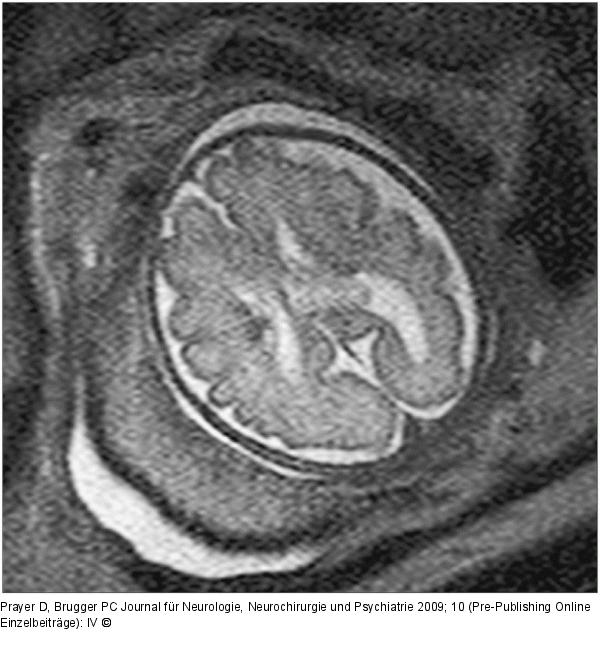

Abbildung 5: Fetus - 30. SSW 30. SSW, axiale Schichtführung. Auf der linken Bildseite zeigen sich, am Rand des Seitenventrikels gelegen, zwei dunkle Knötchen, die subependymalen Riesenzellastrozytomen entsprechen, und für das Vorliegen einer tuberösen Sklerose pathognomonisch sind. |

30. SSW, axiale Schichtführung. Auf der linken Bildseite zeigen sich, am Rand des Seitenventrikels gelegen, zwei dunkle Knötchen, die subependymalen Riesenzellastrozytomen entsprechen, und für das Vorliegen einer tuberösen Sklerose pathognomonisch sind. |